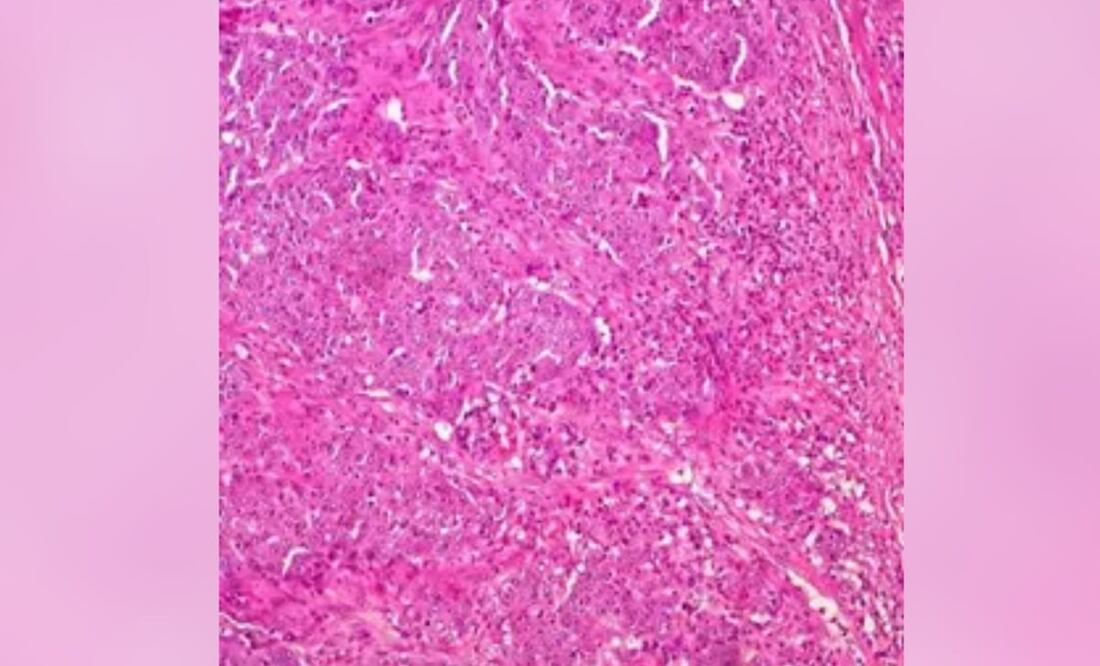

La investigación preclínica es un primer paso para demostrar que el virus oncolítico CF33 de City of Hope puede atacar tumores difíciles de tratar que "esposan" el sistema inmunológico y evitan que las células T activen el sistema inmunológico para matar las células cancerosas. Más específicamente, los investigadores demostraron en modelos de ratón que CF33 parece aumentar la expresión de PD-L1 en las células tumorales y hace que mueran de una manera que estimula la afluencia de células inmunes activadas.

"El CF33 infecta, se replica y destruye selectivamente las células cancerosas. Este estudio demuestra que un virus de diseño que creamos para infectar una amplia variedad de cánceres puede hacer que las células tumorales sean muy reconocibles para el sistema inmunológico", explica.

Para confirmar su hipótesis, los científicos de City of Hope probaron cuatro grupos: control sin tratamiento, anti-PD-L1 solo, CF33 solo y una combinación de CF33 y anti-PD-P1. Los resultados indicaron que un tratamiento combinado del virus oncolítico de City of Hope y anti-PD-L1 pareció ser más eficaz.